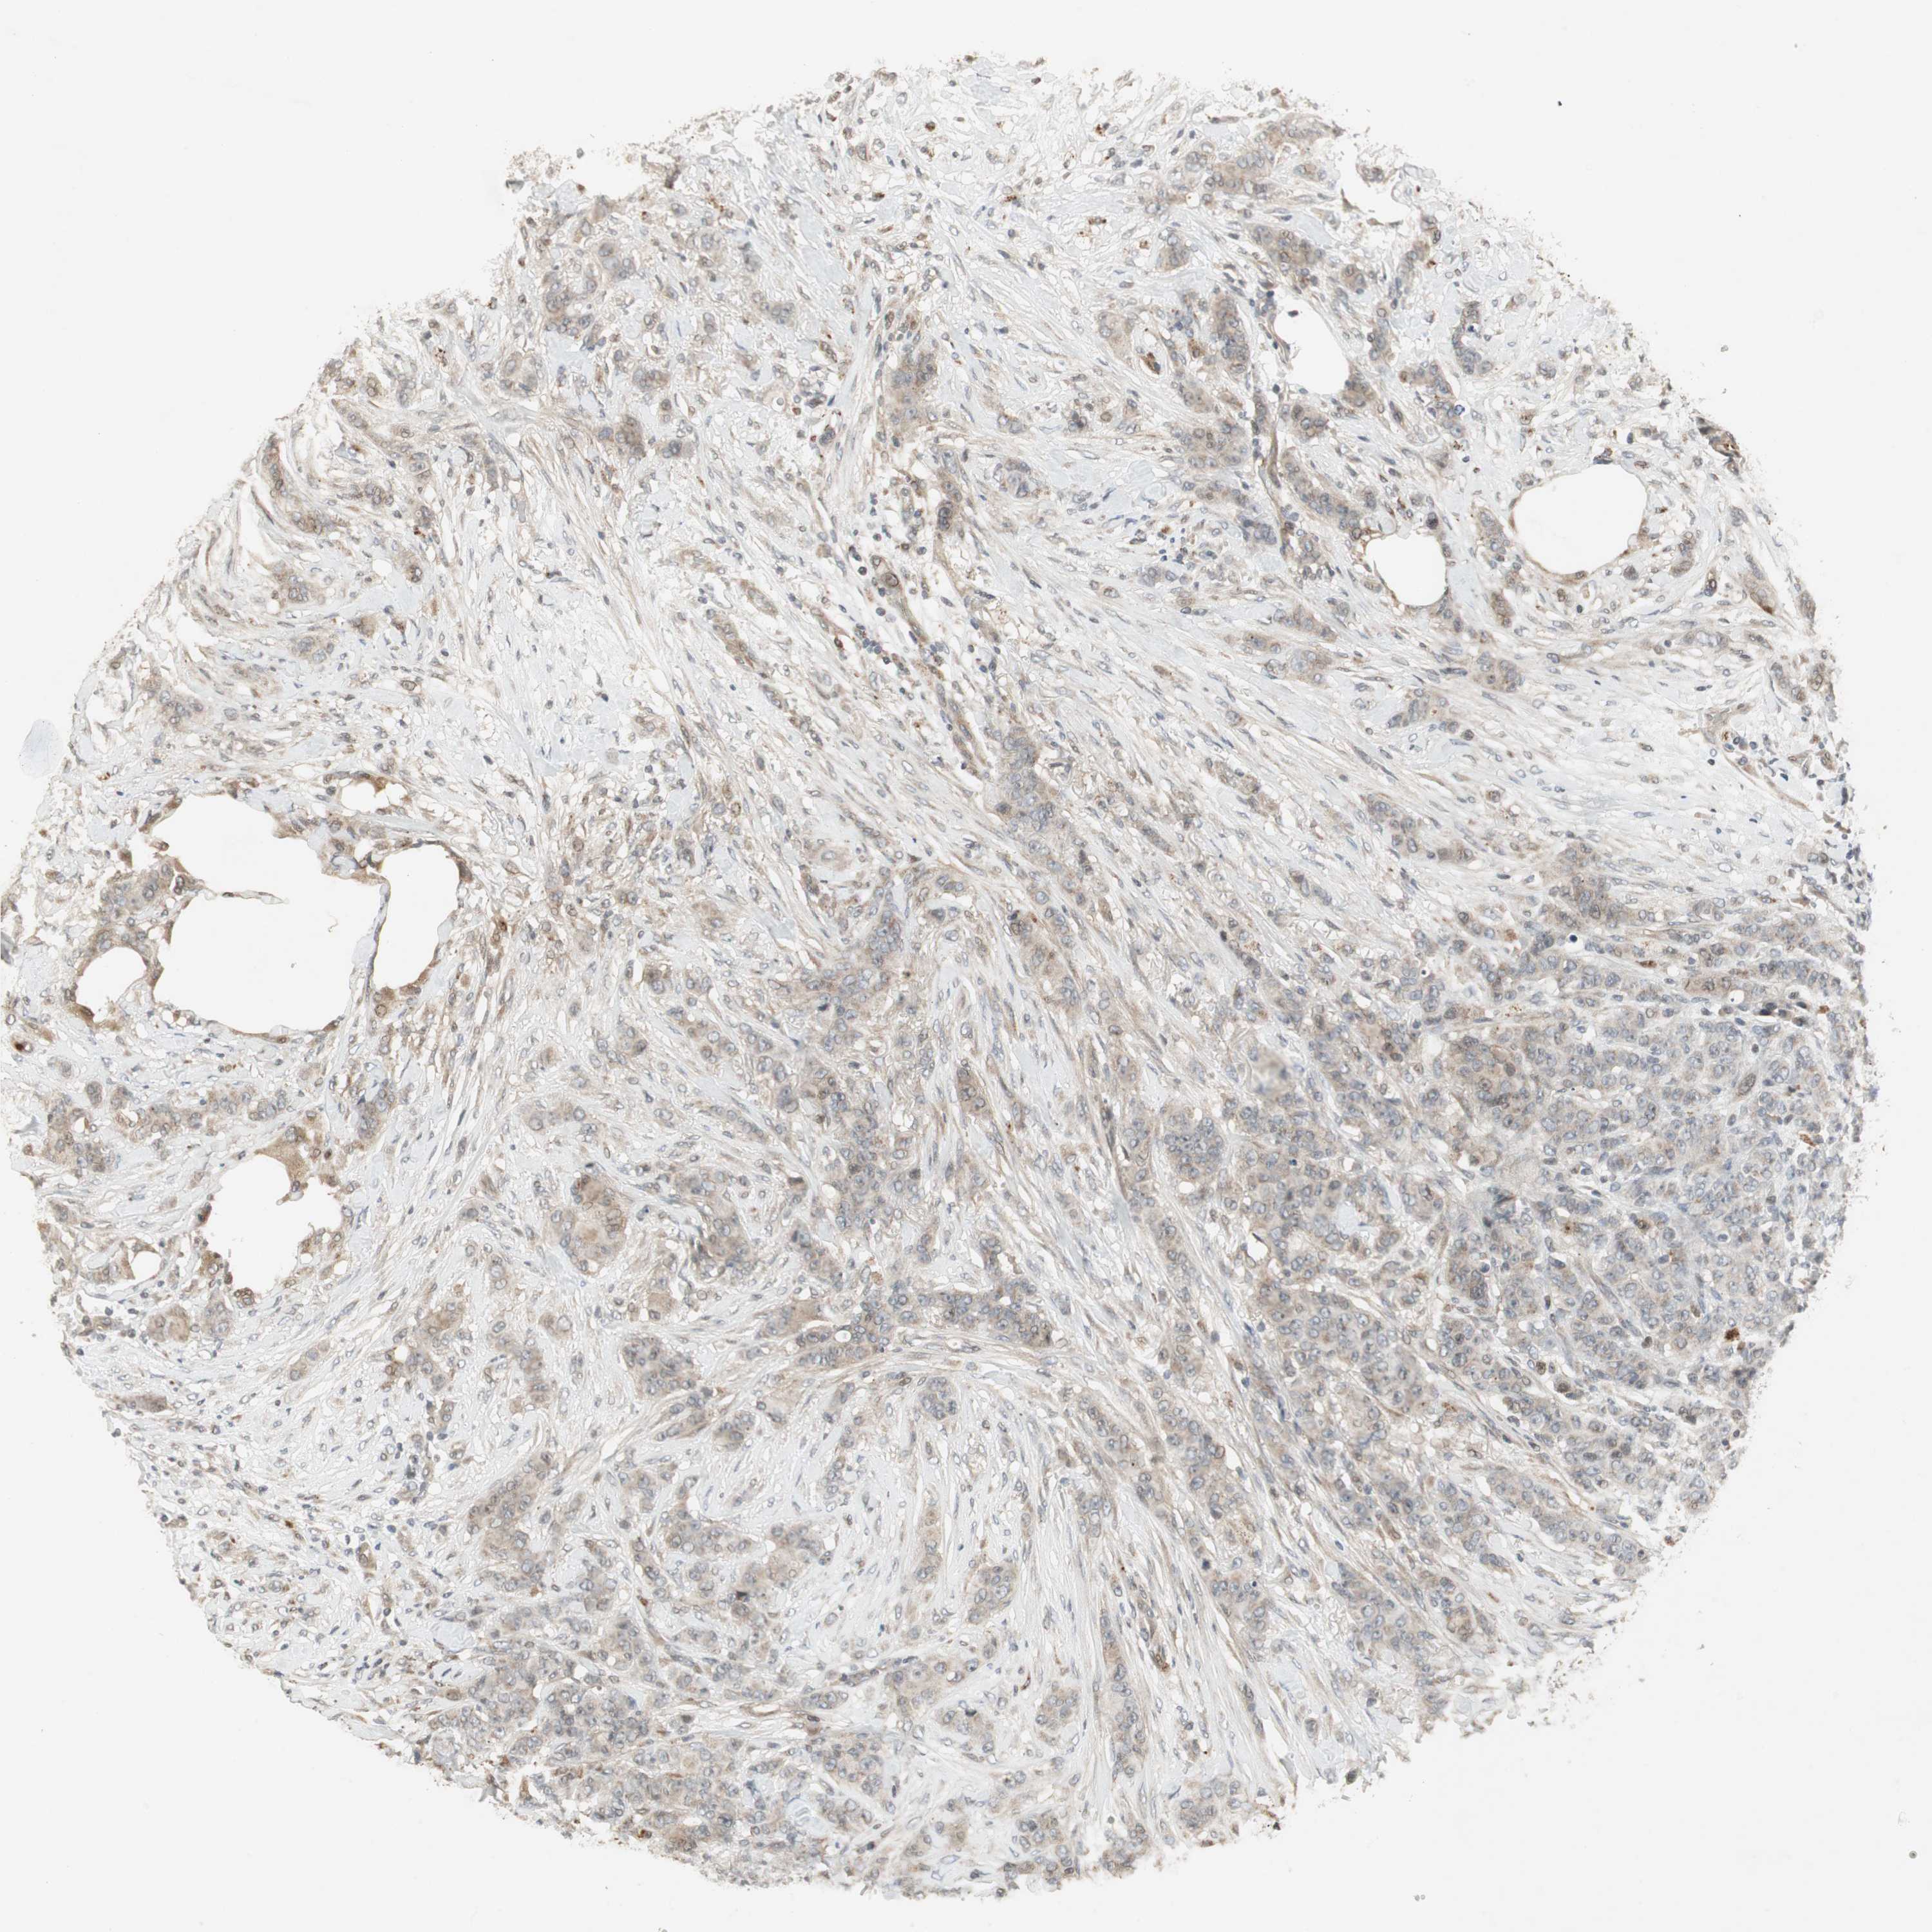

CANCER BREAST CANCER Show tissue menu

BRCA TCGA BRCA VALIDATION PROTEIN EXPRESSION

ANTIBODIES

SNX4 is not prognostic in Breast Invasive Carcinoma (TCGA)